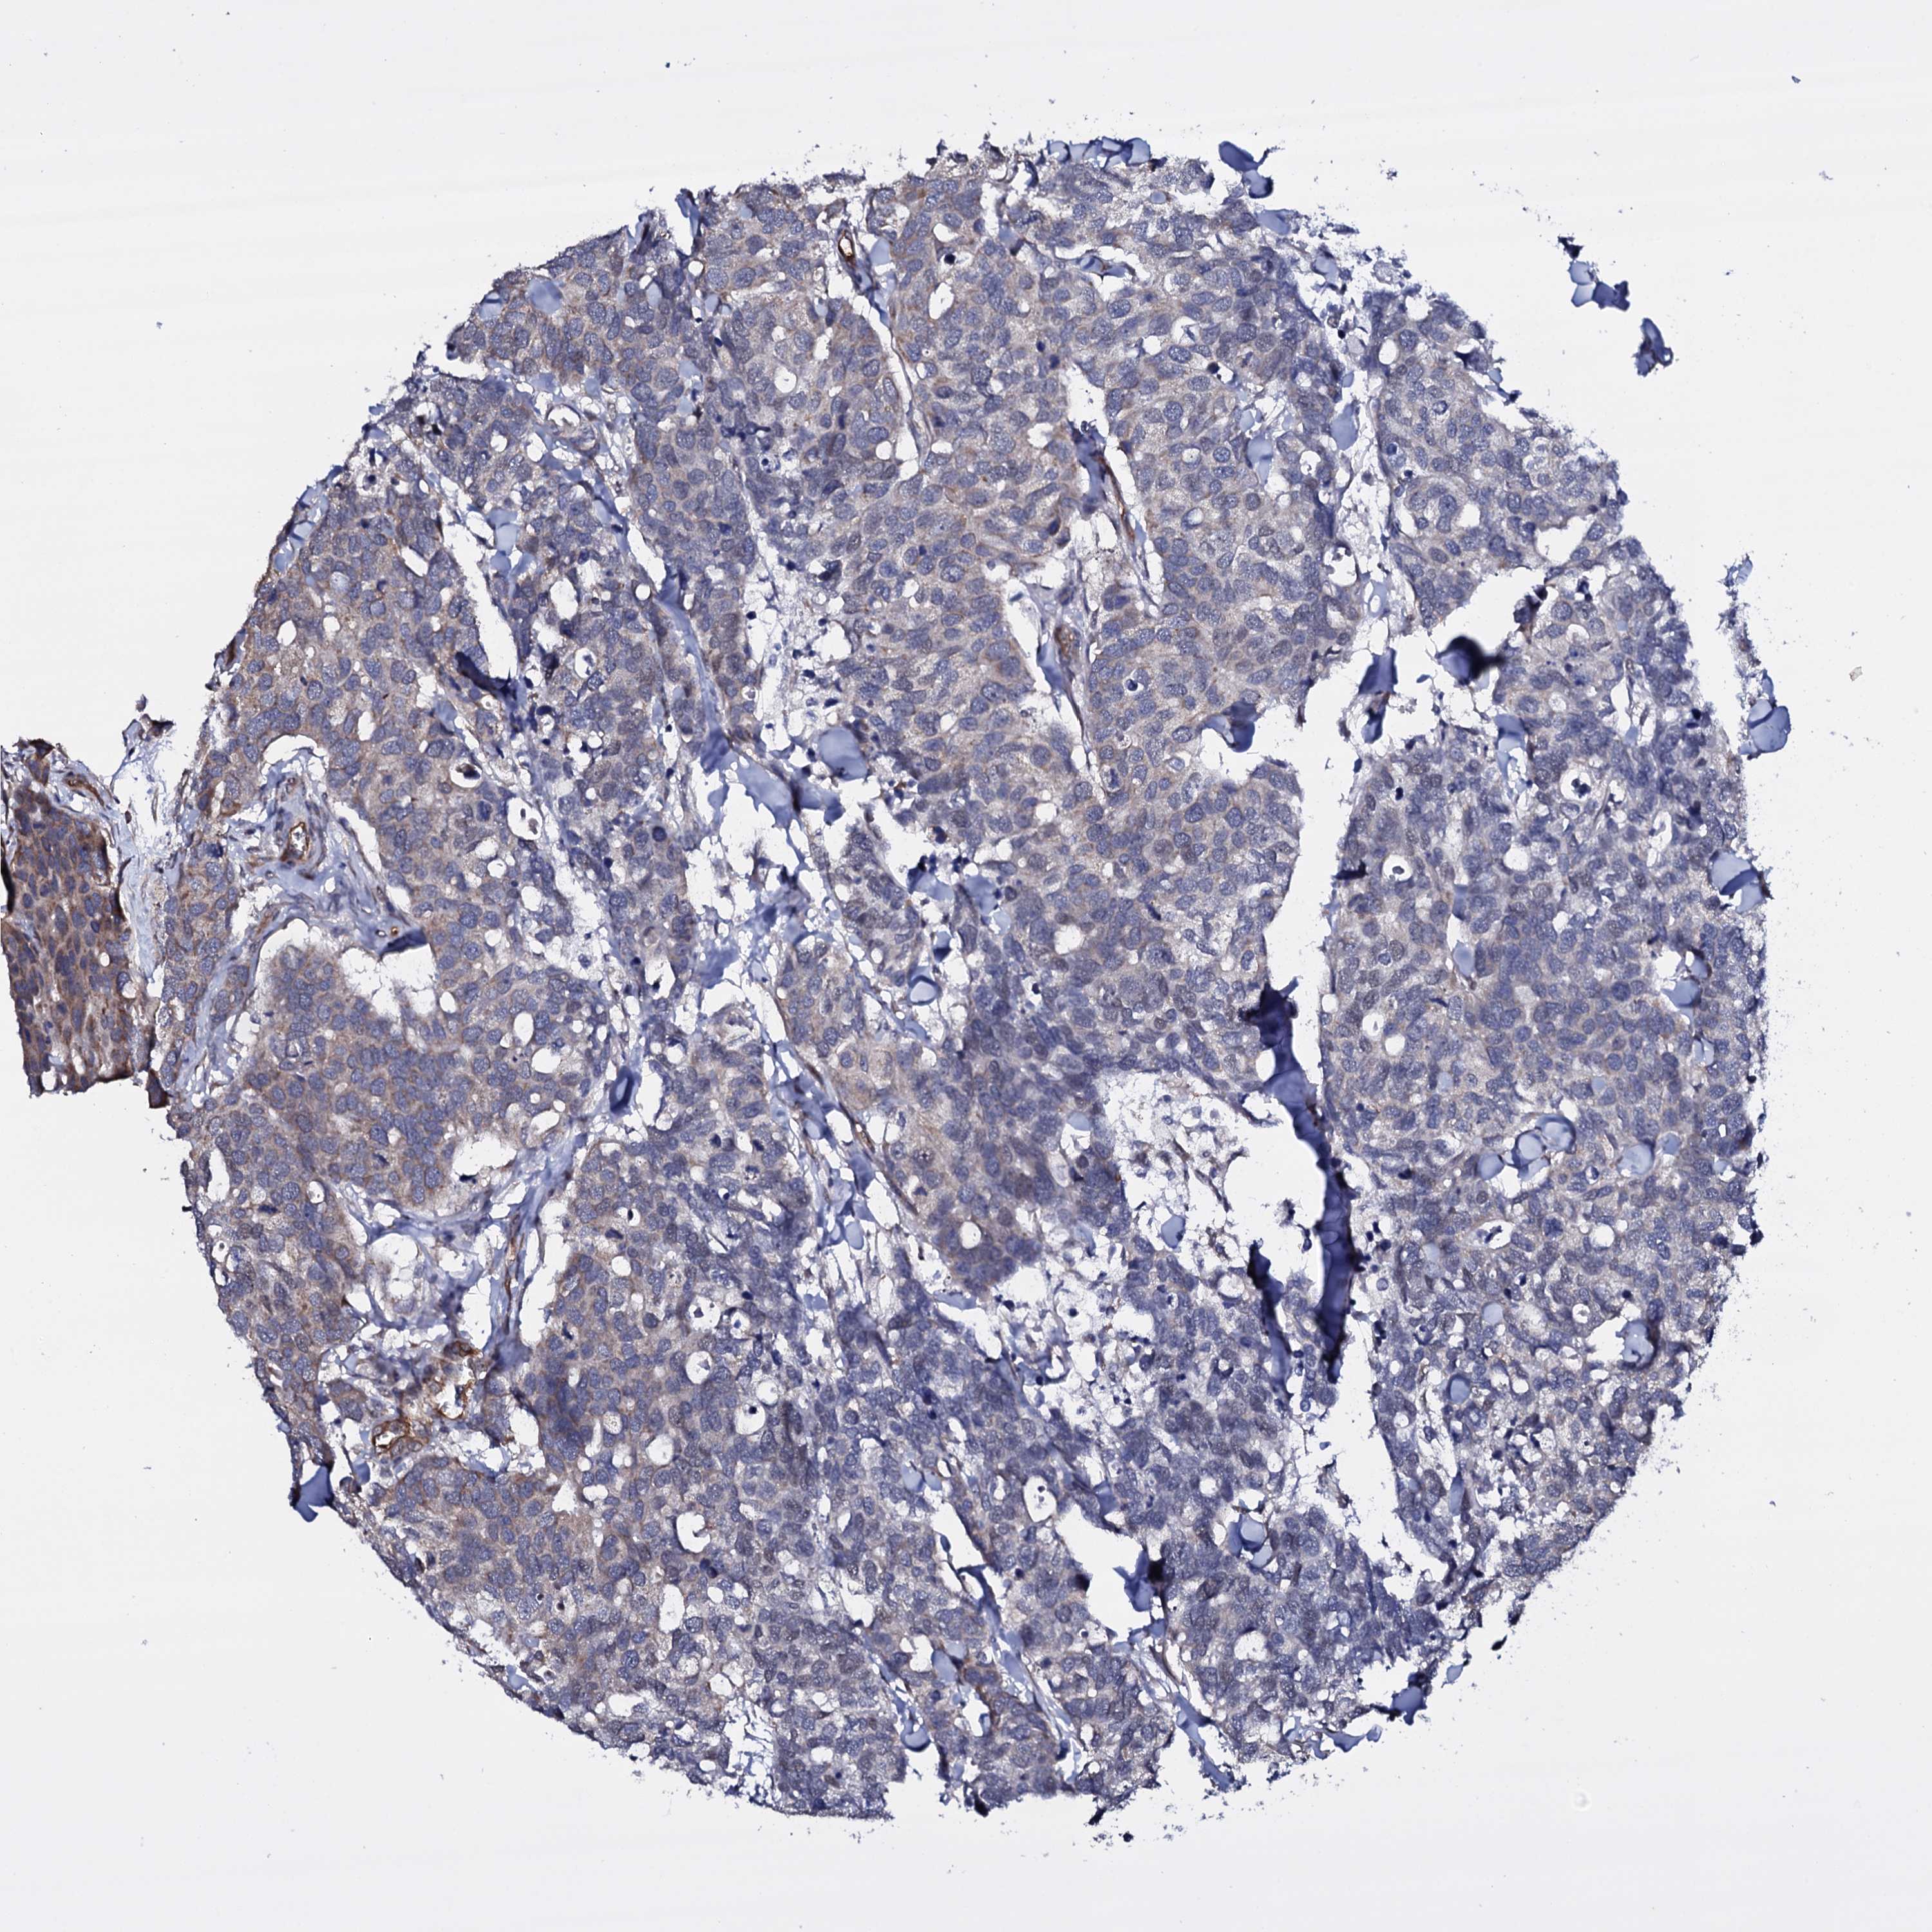

CANCER BREAST CANCER Show tissue menu

BRCA TCGA BRCA VALIDATION PROTEIN EXPRESSION